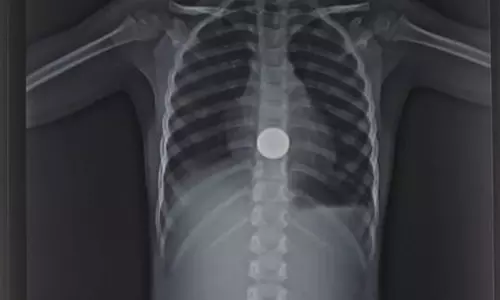

குழந்தையின் உணவுக்குழாயில் சிக்கிய 5 ரூபாய் நாணயம் அகற்றம்

குழந்தையின் உணவுக்குழாயில் சிக்கிய 5 ரூபாய் நாணயம் அகற்றப்பட்டது.